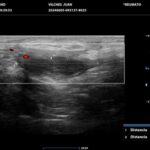

La HS es una enfermedad crónica, inflamatoria inmunomediada, sistémica, recurrente y debilitante de los folículos pilosos terminales con origen en las glándulas apocrinas de estos. Presenta habitualmente lesiones dolorosas, profundas e inflamadas, localizadas más frecuentemente en las regiones axilares, inguinales y anogenitales. El 80% de las lesiones tienen ubicación profunda de difícil acceso al examen físico. Su diagnóstico es clínico pero el ultrasonido (US) de alta resolución con Doppler es un método que cumple actualmente un rol esencial para establecer el diagnóstico, estadificar la enfermedad y detectar actividad, incluso en el caso de lesiones no pesquisadas en el examen físico. También nos permite monitorear el estado y la progresión de la HS, facilitando la evaluación rápida de distintos enfoques terapéuticos. Incluso, los cambios ecográficos pueden modificar la conducta terapéutica.

Los hallazgos ecográficos más relevantes son el ensanchamiento de folículos pilosos, engrosamiento y ecogenicidad anormal de la dermis, nódulos pseudoquísticos dérmicos, colecciones líquidas y tractos fistulosos. Por otro lado, el US nos permite valorar la localización exacta y extensión de las lesiones, su ecogenicidad, el grado de vascularización al examen Doppler y las eventuales complicaciones, e incluso la modificación de las lesiones en respuesta a la terapéutica instaurada. La HS se estadifica clínicamente mediante la clasificación de Hurley y los hallazgos ecográficos muestran correlación con cada estadio clínico.

El diagnóstico ecográfico resulta de importancia diagnóstica, tal es así que la ecografía de alta resolución y el estudio Doppler han ocupado un lugar preponderante en los últimos años. La ecografía de la piel permite identificar lesiones no encontradas en el examen físico, evaluando de manera fehaciente su extensión anatómica. El empleo de la ecografía en la HS es ideal, ya que el 80% de las lesiones ocurren en las capas más profundas y no en la superficie de la piel. Permite evaluar la localización exacta y extensión de las lesiones, su ecogenicidad, el grado de vascularización al examen Doppler, las eventuales complicaciones, e incluso la respuesta terapéutica.

El estudio ecográfico de alta resolución con Doppler tiene un rol fundamental en la categorización de las lesiones de HS en profundidad, incluso las subclínicas. Debemos incluir al US como técnica de elección para estadificar y monitorear pacientes con HS, ya que nos permite acceder a un diagnóstico rápido de lesiones típicas con las que podremos, en conjunto con la clínica, estadificar y seguir en el tiempo a los pacientes.